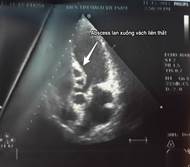

Kết quả siêu âm tim qua thành ngực cho thấy hình ảnh sùi van động mạch chủ, áp xe thành trước động mạch chủ lan tới 1/3 trên vách liên thất gây hở chủ nhiều. Sùi van hai lá gây hở hai lá nhiều và giãn các buồng tim (Hình 1,2). Điện tim đồ cho thấy block nhĩ thất cấp 3 (Hình 3). Cấy máu cấp ở 3 vị trí khác nhau cho kết quả âm tính. Bệnh nhân được hội chẩn nội – ngoại khoa và được chỉ định phẫu thuật cấp cứu.